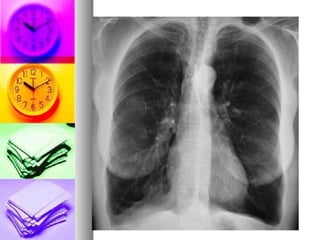

 Imagerie thoracique

 Rx thorax (F/P):

- Peu sensible et peu spécifique

- Cherche éventuellement les comorbidités

(cancer bronchique ,pneumopathie, cardiopathies)

-   Peut montrer des signes de distension

    Rx thorax (F/P) signes distension :

-   un aplatissement des coupoles

diaphragmatiques

-   une horizontalisation des cotes, une

hyperclarté

-   un cœur en goutte (Le coeur est petit,

allongé,se décolle de la coupole)

   Rx thorax (P) signes distension :

-   une ↑ de l’espace clair retrosternal et

retrocardiaque (profil)

-   une ↑ diamètre thoracique

ANT/POST(profil)